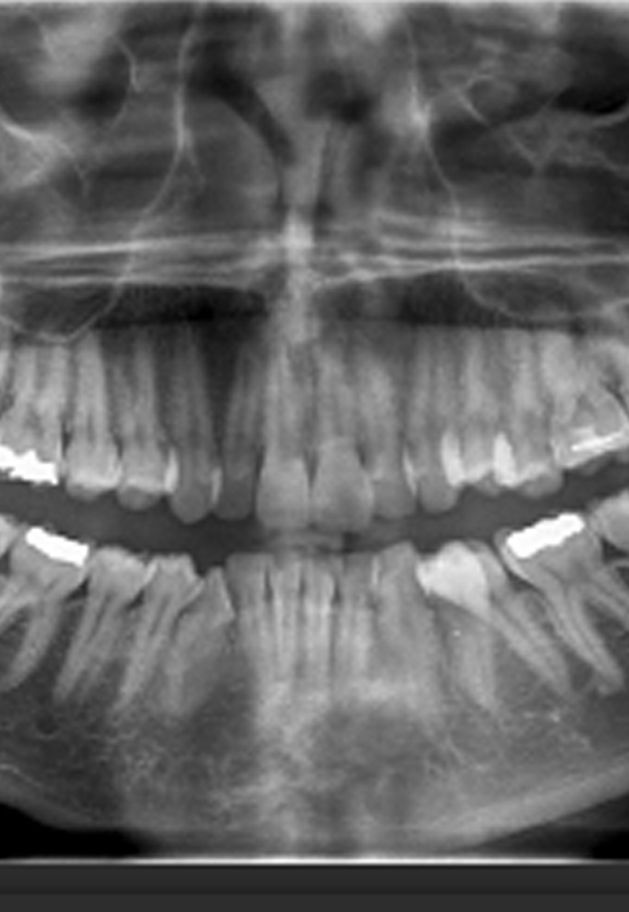

ΑΞΙΟΛΟΓΗΣΗ ΟΡΘΟΠΑΝΤΟΜΟΓΡΑΦΗΜΑΤΟΣ

Με την αξιολόγηση του παντομογραφήματος, ο Ορθοδοντικός έχει την δυνατότητα να αξιολογήσει να αξιολογήσει διάφορες παθολογικές καταστάσεις στα δόντια, στα οστά των γνάθων, στην κροταφογναθική διάρθρωση ή σε άλλες εμφανείς δομές του προσώπου κατά την αξιολόγηση της ακτινογραφίας.